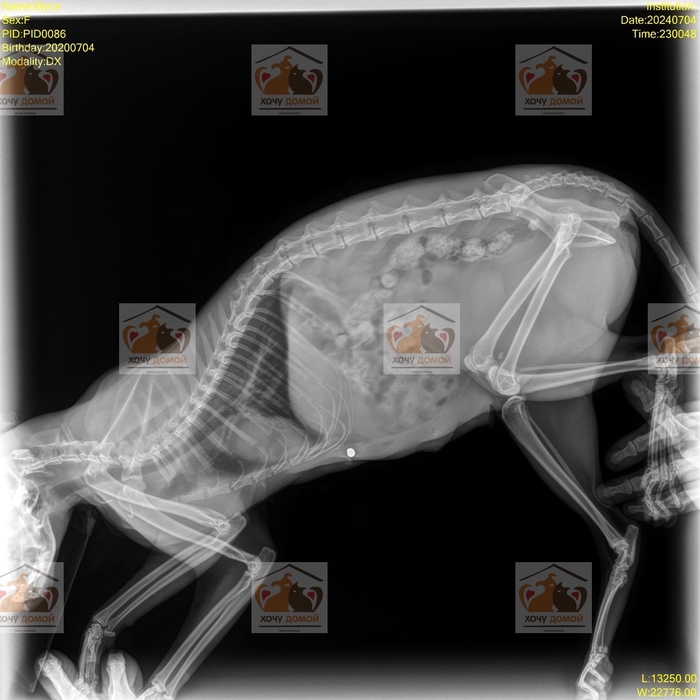

Мы думали, что видели всё. Но это максимальный кошмар. Люди попросили помощи для кошки и ее котенка. Сначала думали, что они попали под машину. Но, когда сделали рентген, пришли в ужас. Кошку и котенка кто-то расстреливал. В прямом смысле.

На рентгене обнаружены пули!

И если с кошкой все более менее понятно, у нее все шансы встать на лапы, то котенок не встает на лапки, не может самостоятельно ходить в туалет.

Ему требуется консультация невролога и возможно операция. Судя по наполненности мочевого пузыря, котенок в таком состоянии не долго. Возможно есть шансы на восстановление 🙏🏻 Мы не врачи, поэтому не знаем сейчас что сказать.

Завтра едем к неврологу. Как обычно, нужно оплачивать такси, прием специалиста, а дальше уже по обстоятельствам 😞 Посмотрим как оно будет… Верим.